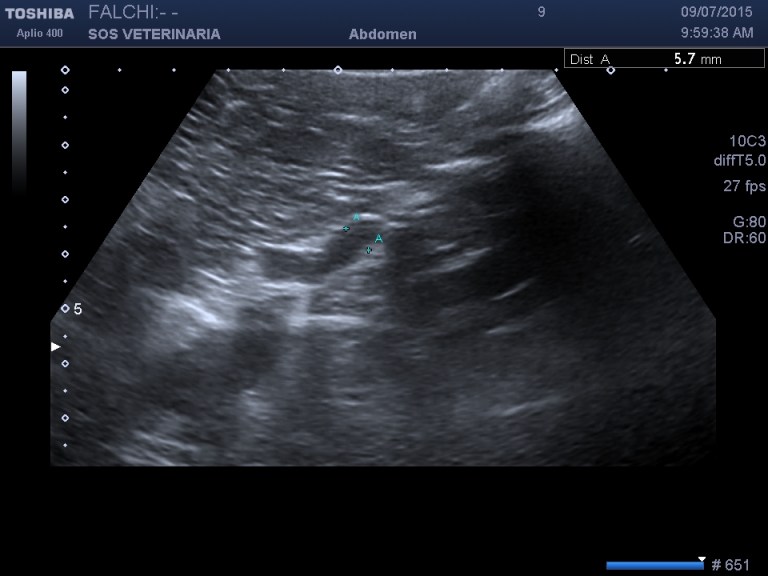

primo esame ecografico .volume surrenalico nei limiti,morfologia surrenalica rispettata , ,lesione focale epatica compatta omogenea nei settori di sx altre piu’ piccole lesioni focali meno demarcate e definite sempre nei settori di sx

ecografia di secondo livello con CEUS

fase arteriosa isoenanchement

fase portale e tardiva ipoenachemente